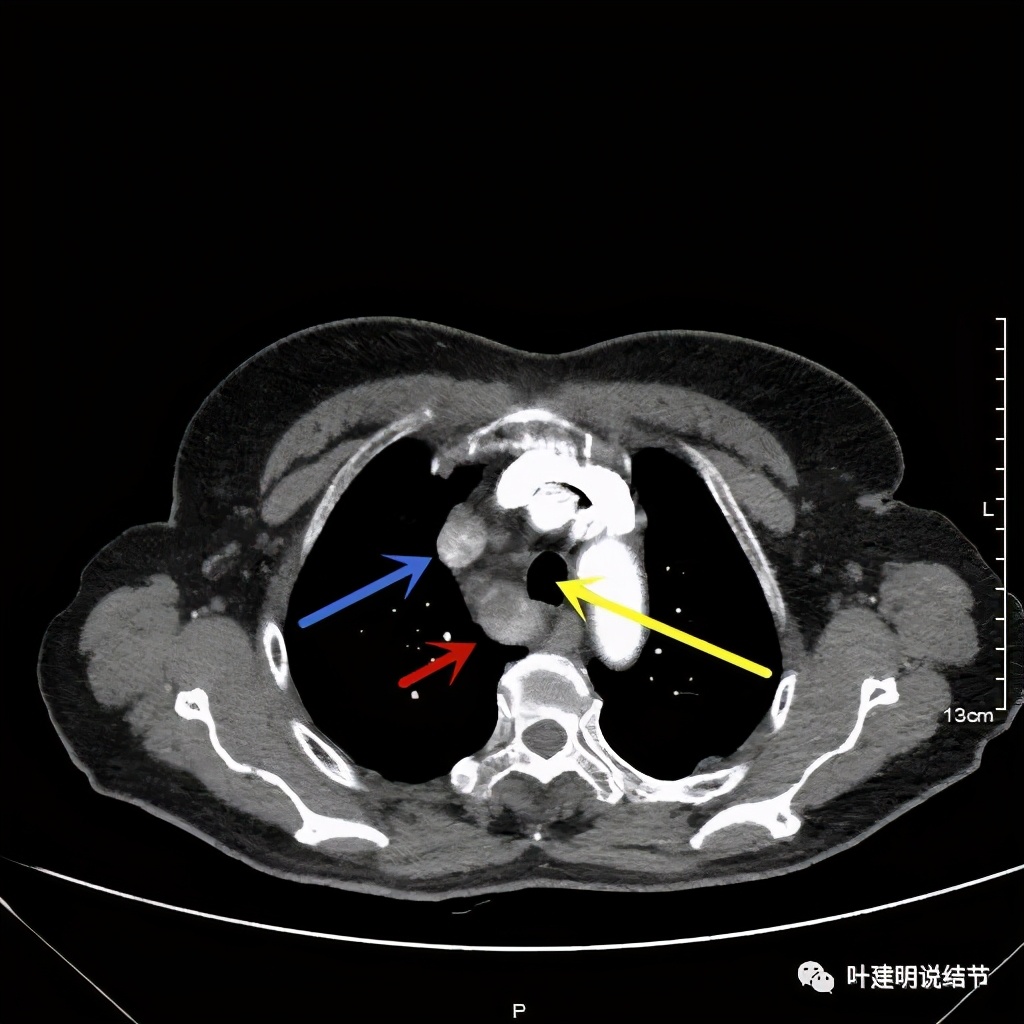

上图红色示肿瘤,黄色示气管,粉色示肿瘤与气管关系密切,桔色示左无名静脉,蓝色示上腔静脉,而且肿瘤密度不均杂乱

上图红色示肿瘤,黄色示气管,桔色示左无名静脉,蓝色示上腔静脉,而且肿瘤密度不均杂乱